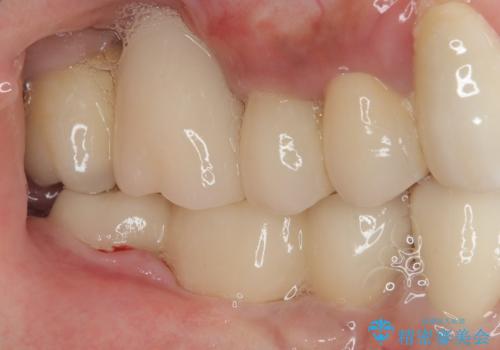

抜けてしまった奥歯 短期間インプラント治療

- インプラントが脱落してしまったとのことで来院された患者様です。

歯肉は綺麗に治癒しており、インプラント埋入に十分な骨があったため、速やかにインプラント埋入を行うこととしました。

インプラント埋入の状態が良ければ即日で仮歯を装着し、十分な生着が確認され次第、オールセラミッククラウンにて補綴治療を行うこととしました。

インプラントの初期固定も埋入後の生着もスムーズであったので、埋入から3ヶ月で無事に治療を終えることができました。